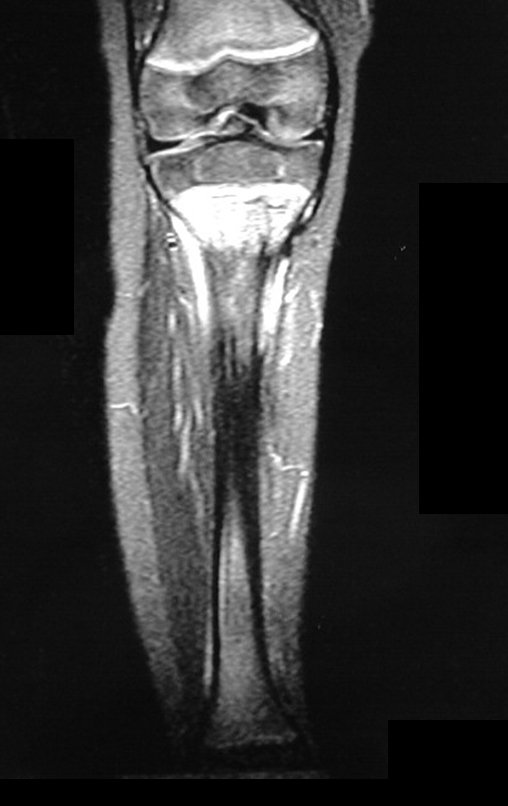

Ewing sarcoma of the tibia

In December 2006, the patient underwent surgery to resect the proximal metaphyseal segment of the tibia, including the growth plate, and self-transplantation of the growth cartilage of the proximal segment of the fibula, through transfer to the tibia, without microsurgery.